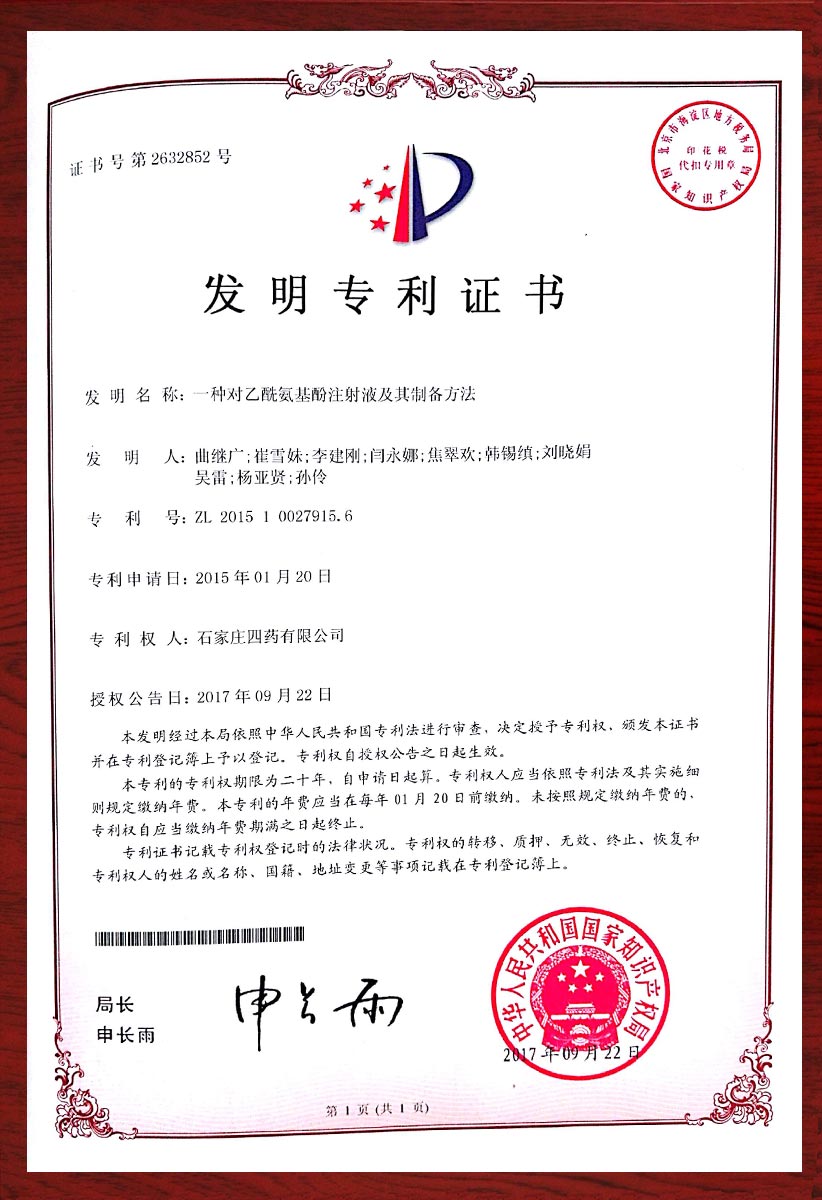

专利证书